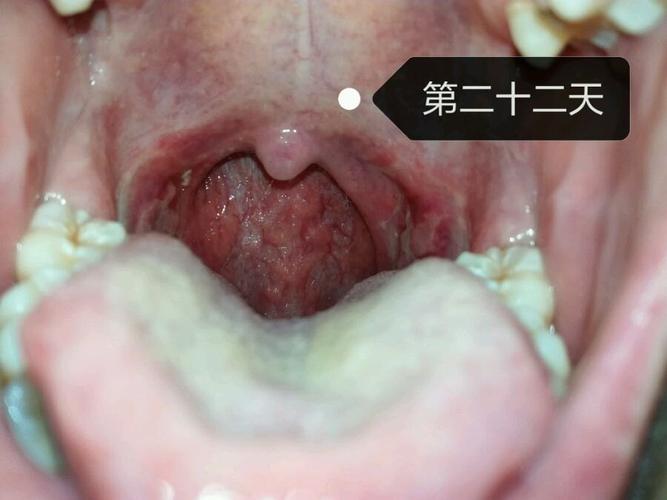

扁桃体术后白膜脱落过程图

扁桃体术后白膜

扁桃体术后图片

扁桃体术后恢复照片

扁桃体术后恢复过程图

扁桃体手术后痊愈图片

扁桃体手术伤口恢复图